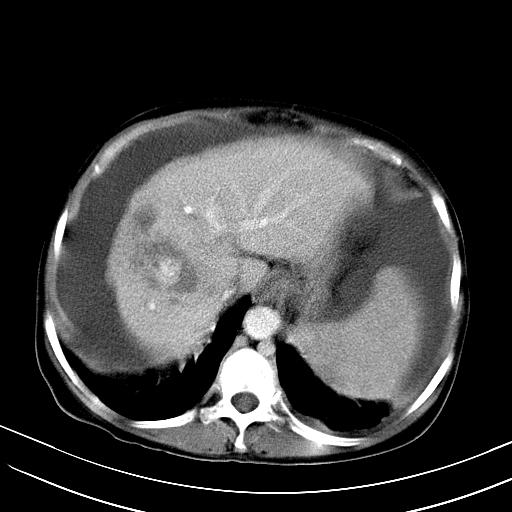

1)肝右叶肝癌并肝动静脉漏。2)肝硬化,腹水。3)胆囊炎。

肝右叶肝癌并动静脉漏,肝硬化,腹水。

1)肝右叶肝癌并肝动静脉漏 门v右支瘤栓伴海绵样变。2)肝硬化,脾大 腹水。3)胆囊炎。门v高压.

1)肝右叶肝癌并肝动静脉漏。2)肝硬化,腹水。3)胆囊炎。 4,脾大,脾囊肿

右叶肝癌并肝动静脉漏(动脉期肝动脉及门静脉内均可见造影剂),肝硬化,腹水。(胆囊壁水肿)

1)肝右叶肝癌,考虑并发肝动静脉漏。扫描时间好像慢了。2)肝硬化,门脉高压、脾大、腹水。